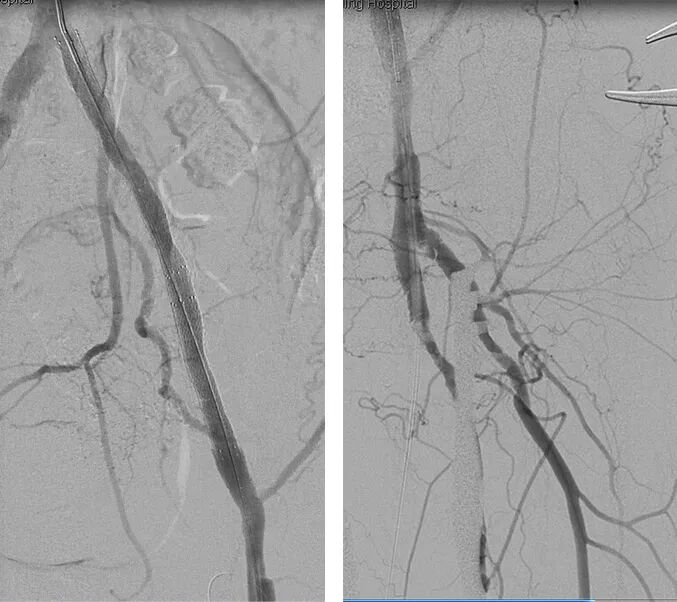

3. 于左侧股浅动脉引出导丝,以血管滑线缝合股总动脉以及股深动脉切口,沿导丝引入8F短鞘,导引3.5mm球囊扩张后,未防止充分预扩导致血管破裂,先行植入支架(依次于髂外植入8*100mm覆膜支架、髂总动脉植入8*80mm支架、髂外动脉腹膜支架内嵌入8*60mm支架),导引8mm球囊进行后扩张,扩张后支架形态如下:

4. 最后造影显示:左侧髂总、髂外、股总、股深动脉显影良好,左侧髂内动脉可见显影;